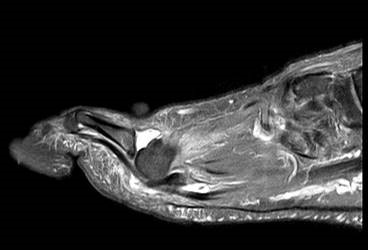

Eine Röntgenaufnahme unter Belastung mit Abbildungen des ganzen Fußes a. p. (mit 15-20° Röhrenkippung) und seitlich, sowie Schrägaufnahmen, reichen meist zur Diagnose. Manchmal ist ein MRT und DVT ergänzend hilfreich. Selten wird die Indikation für ein SPECT CT gestellt (Abb. 6).

Bei den proximalen Überlastungsschäden mit Arthroseentwicklung im Übergang zur Fußwurzel am TMT II, seltener TMT III, beklagen die Patienten Schmerzen an der Fußwurzel vor allem beim Barfuß laufen oder in leichtem Schuhwerk. Auch kommt es häufig zu einer Affektion des N. peronaeus profundus, wenn ein dorsaler Osteophyt der tarsometatarsalen Gelenke vorliegt und der Nerv durch den Druck des Schuhs gegen die Knochenkante gedrückt wird. Die Kompression des Nervens ruft Beschwerden eines vorderen Tasaltunnelsyndroms hervor mit Dysästhesien oder Schmerzen im Nervenverlauf bis in den Interdigitalraum D1/2.

• konventionelle Röntgenbilder mit Belastung im Stehen a. p. und seitlich, ggf. schräg (Abb. 9, 10 und 11).